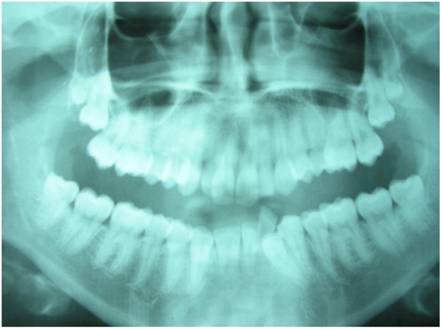

Figure 5

X-Ray Dental Panoramic Tomogram (younger sister)

The radiologic evaluation of the two sisters allowed to determine as follows:

The elder sister had nine impacted teeth; these were 1.8 - 1.9 - 2.8 - 2.9 - 2.10 - 3.8 - 3.9 - 4.8 - 4.9 (Fig. 4), while the youngest sister had four impacted teeth, that is 1.8 - 1.9 - 2.8 - 2.9 (Fig. 5).